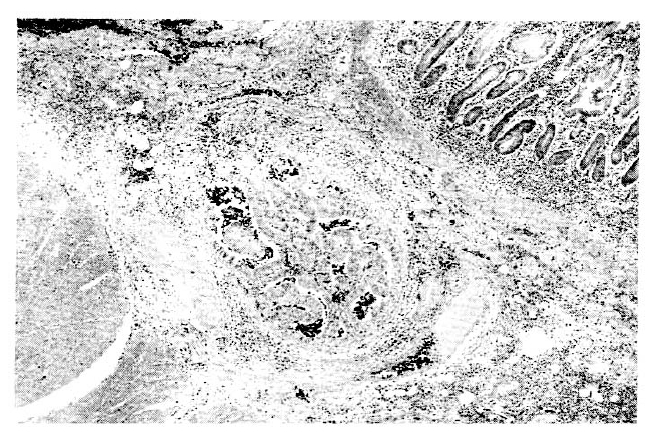

Sections from the gastro-jejunostomy site showed moderately well differentiated adenocarcinoma of the stomach, which directly extended into the anastomosis site of the jejunum (Fig. 4)

Fig. 4.

Sections from the gastrojejunostomy site show moderately well differentiated adenocarcinoma of the stomach, which is directly extended into the anastomosis site of the jejunum.

Also the tumor was diffusely infiltrated throughout all layers.